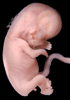

Human Embryo

Carnegie Stage 23 (56 post-ovulatory days)

Most embryos at stage 23 are approximately 56-57 postovulatory days old and measure 23-32 mm in length. Distinguishing criteria for this stage include fusion of the eyelids at the medial and lateral margins, clear distinction of the subdivisions of the upper and lower limbs, the forearms appear at or above the level of the shoulders, the superficial vascular plexus of the head is very close to the vertex, and the external genitalia are well developed but not always sufficiently to distinguish the embryo's sex.

(NOTE: These specimens are late stage 23.)